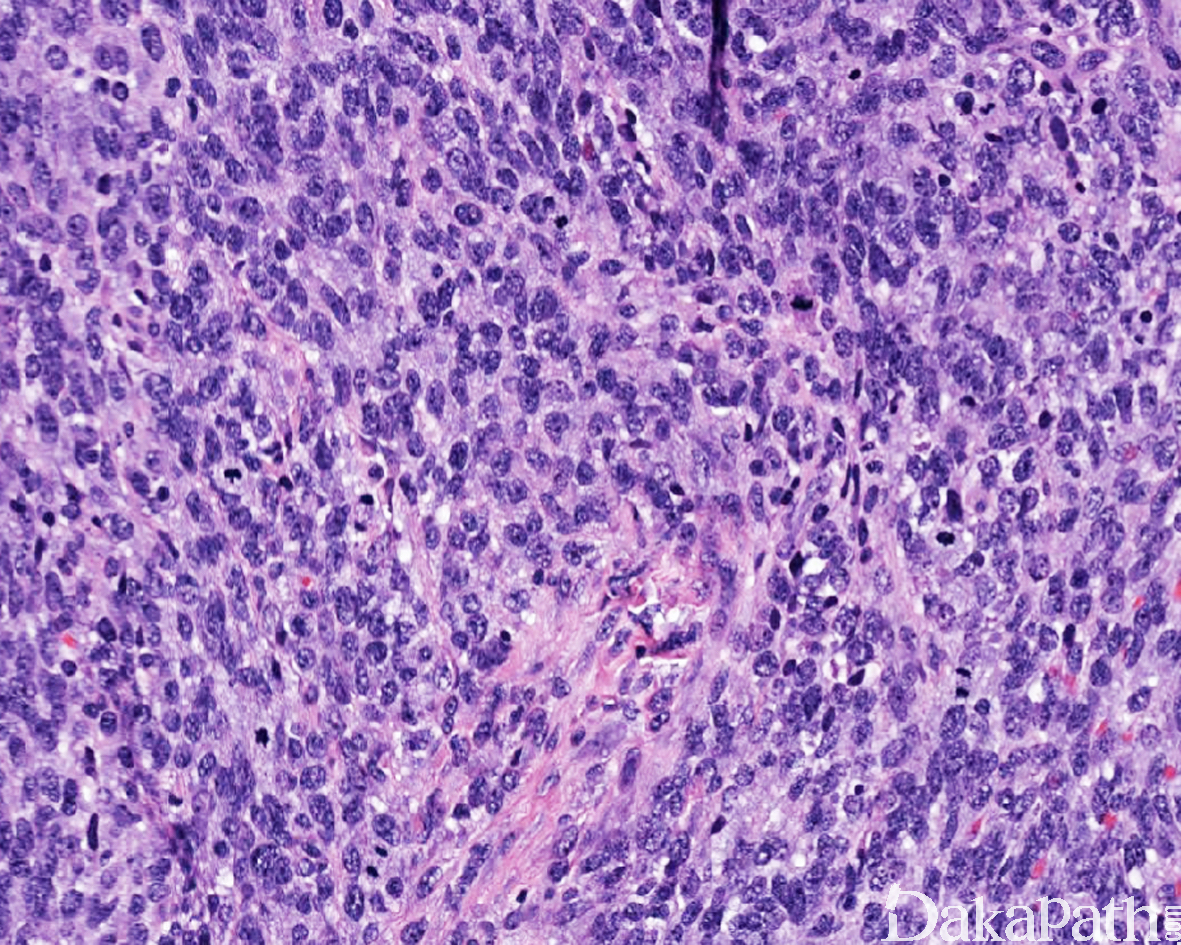

低倍镜下显示实性成片的小到中等大的圆细胞增生,约 1/3 可见胶原纤维分隔的结节状或模糊结节状生长;少见的结构特征包括交错束状或网状排列

约 1/3 可见不同程度的黏液性间质改变;

瘤细胞圆形或卵圆形为主,约 10%可见混合的梭形细胞,偶尔可以梭形细胞为主;约 23%可见混有浆样细胞或 Rhabdoid(横纹肌样)细胞,偶尔可以后者为主;约 20%可见三种形态细胞的混合(圆形/卵圆形,梭形,浆样/横纹肌样细胞);

瘤细胞胞浆稀少至中等量,淡嗜酸性或透明,浆样/横纹肌样细胞具有相对丰富的胞浆;

核染色质形态变化不等,半数以上染色质空泡状,30%可见颗粒状纤细的染色质,约 20%可见深染的染色质;约 1/3 可见多灶性明显的核仁;

核大小相对一致,轻度多形性,少数可见散在的中等程度的多形性核;

核分裂象活跃,平均 32 个核分裂象/10HPF;

绝大多数肿瘤可见多灶性的地图性坏死。